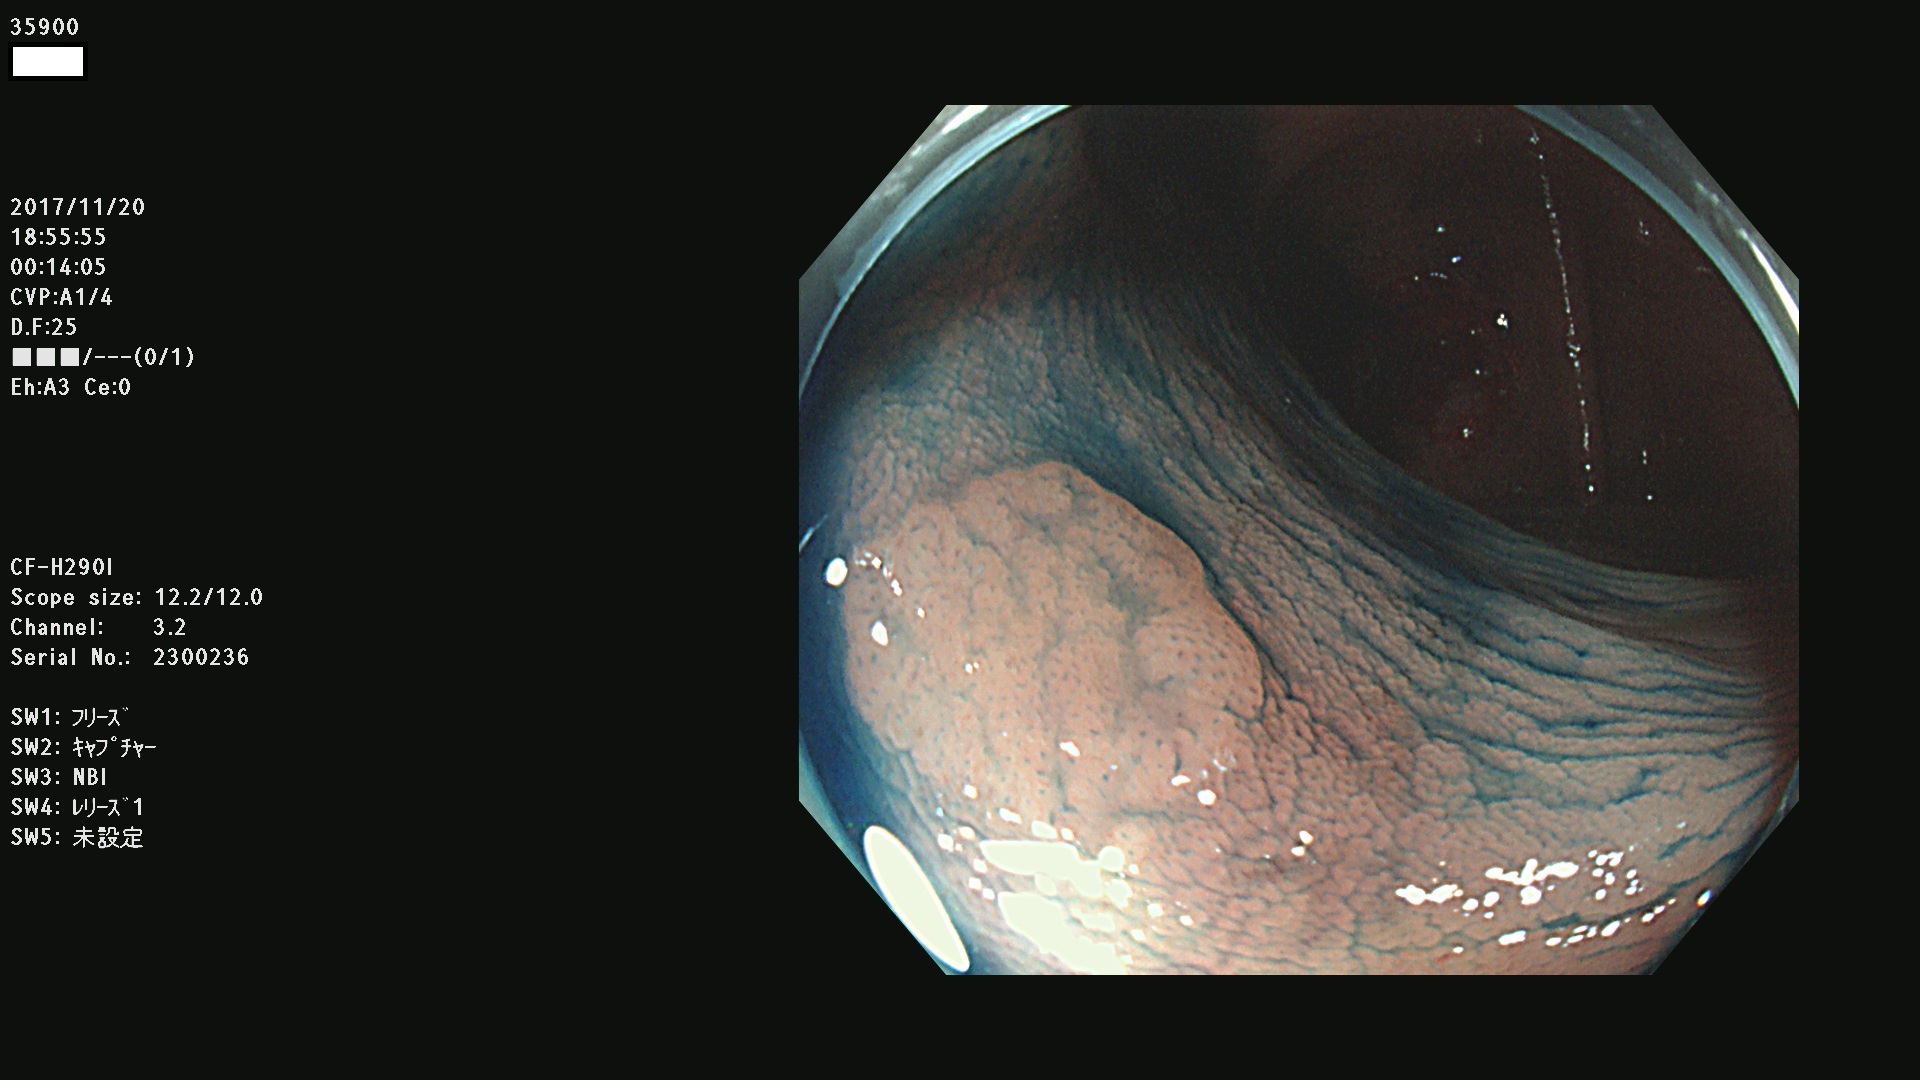

腺腫発見率43 % (カルテ番号 35900〜35999の100名の方の検査結果で集計)大腸癌検診最新情報

以下のカルテ番号の方に腺腫(Adenoma,Group3〜5)が見つかりました(集計法)

35900 35901 35904 35908 35912(SSA/Pのみ) 35914 35918 35922 35925 35926 35928 35931 35932 35933 35934 35937 35939 35943 35945 35947 35949 35951(SSA/Pのみ) 35952 35958 35959 35963 35964(SSA/Pのみ) 35965 35970 35972 35976(SSA/Pのみ) 35977 35978 35979(SSA/Pのみ) 35980(SSA/Pのみ) 35982 35983 35985 35991 35993 35995 35997 35999

発見困難で危険性の高い平坦型病変(上記100名より抽出) ![]()